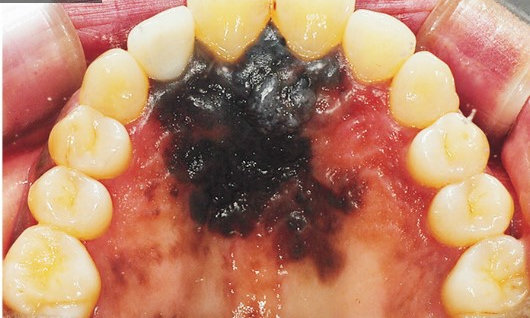

Меланома слизистых оболочек (МСО) – довольно редкое заболевание, существенно отличающееся от меланомы, развивающейся на других покровах и частях тела. Для медицины такая болезнь представляет большой интерес в связи с агрессивным ростом новообразований и менее благоприятным прогнозом для пациентов.

Болезнь наиболее опасна тем, что примерно в трети случаев ее признаки отсутствуют, то есть меланома протекает бессимптомно. Другие две трети пациентов отмечают следующие первые признаки заболевания:

• изъязвление слизистой оболочки;

• кровотечения в зоне поражения опухолью;

• узловатое или мокулярное новообразование, которое может иметь различные оттенки – красноватый, коричневый, фиолетовый, черный, серый, белый;